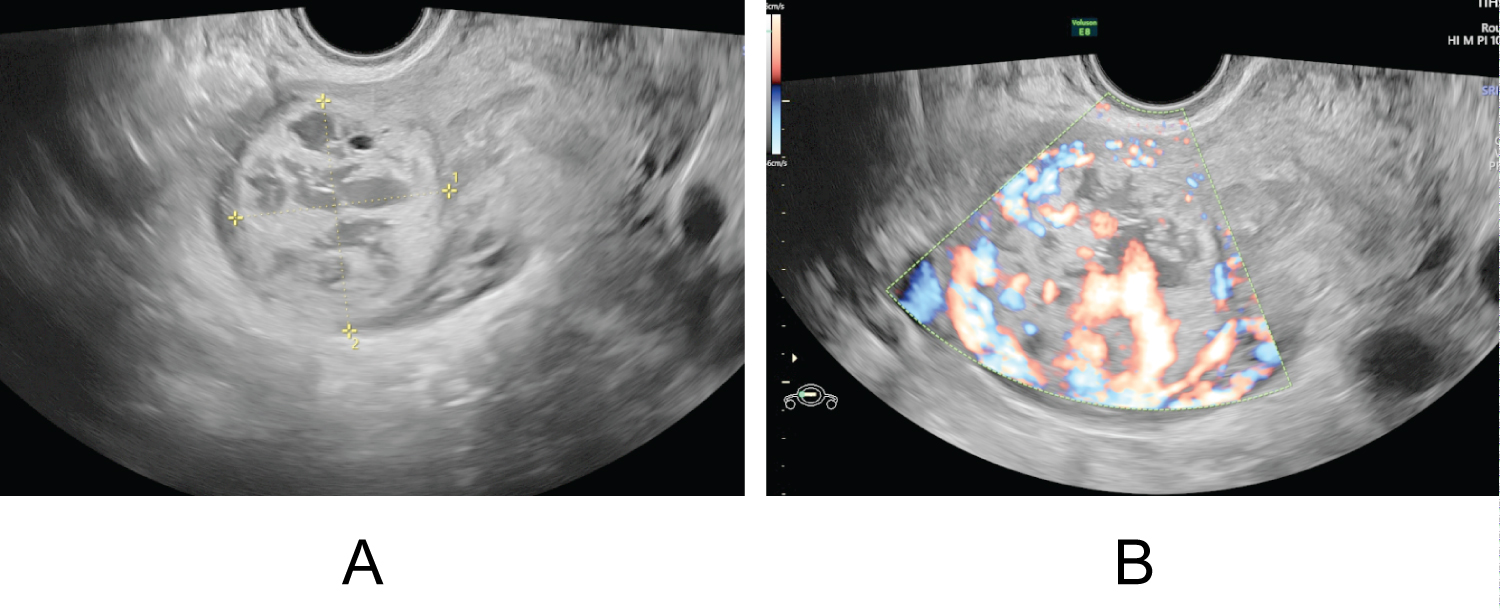

A 33-year-old woman, gravida 4 para 1, presented with vaginal bleeding, slight chest tightness and nausea, underwent a curettage at 5 weeks' gestation for incomplete abortion. While the level of serum β-HCG showed 39576 IU/L on post-surgery day and continued to rise during the following 2 weeks. On the day being transferred to our hospital, the level of serum β-HCG manifested 168208 IU/L, and the transvaginal sonography (TVS) denoted a mass with uneven echo and abundant blood flow in the right lateral wall of uterus, measuring 38 × 43 × 40 mm (Figure 1a and Figure 1b). On the second day of admission, the β-hCG value rose to 216338 IU/L, along with the mass growing to 41 × 44 × 52 mm. However, the chest computed tomography (CT) and craniocerebral CT revealed no abnormalities. Combining with the pathological result of her previous curettage which indicated necrotic villi, decidual tissue and some trophoblast cells, the preliminary diagnosis of GTN and the decision to initiate EMA/CO chemotherapy regimen were made. Two days later, the serum β-HCG ascended to 225000 IU/L, and the ultrasound did not see the reduction of the mass. Due to the unsatisfactory effect, a surgical method was adopted on the tenth day. During the hysteroscopy exploration, a projection surrounded by abundant and tortuous vascular vessels was seen. Rapid pathology manifested the endometrium clamped by forceps did not contain any abnormal composition, leading to the exploratory laparotomy which showed a bulging mass measuring 50 × 50 mm with a purplish-blue-colored surface below the right horn of the uterus (Figure 2a). The chorionic villous tissues bulged out after a fusiform incision was made by a coagulation hook (Figure 2b), then the product of conception was completely removed and the wound was continuously sutured. Intraoperative pathology showed oedematous villi and proliferous trophoblast cells, so the diagnosis of the hydatidiform mole was considered. Given such consequence, adjuvant chemotherapy continued after surgery. One day postoperatively the patient's β-hCG titer dropped to 37955 IU/L and then decreased to 711 IU/L on the tenth day, at which point she was discharged. A follow-up demonstrated the β-hCG level returned to normal. Ultimately, postoperative pathology in combination with immunohistochemistry analysis (P57+) confirmed chorionic villi surrounded by myometrium with no identifiable fallopian tube, validating the diagnosis of intramural ectopic pregnancy (Figure 3a and Figure 3b).

Figure 1: (a) Transvaginal scan showed a mass with uneven echo in the right lateral wall of the uterus; (b) Doppler flow revealed abundant blood flow signals. View Figure 1